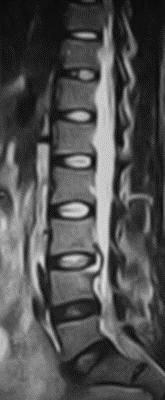

32 years old lady presented with worsening back pain for 4 weeks duration following elective caeseran section done for malpresentation. There was history of repeated attempts of puncture for spinal anaesthesia . She was cathetrised which was removed on day 2 and she has received intravenous broad spectrum antibiotics for 5 days duration. Her surgical wound healed well with no documentation of fever, abdominal pain, cough, dysuria or discharge per vaginum. At presentation her pain was predominantly in lower lumbar region ( VAS – 9/10) with severe paraspinal muscle spasm. She was not able to sit for few minutes and had difficulty in turning in bed . she couldn’t nurse her child due to pain with inability to assume comfortable postures. Root tension signs were negative with no neurological deficits. Radiographs revealed L3/4 disc space reduction with end plate changes. Hematological evaluation showed  elevated TLC, ESR,CRP ( Table 1) . Septic screening for urine , blood and chest infection was negative. MRI showed evidence of spondylodiscitis at L3/4 (FIG 5,6) . She underwent CT guided biopsy which was negative. She later underwent PLIF L3/4 and had grown pseudomonas from the necrotic disc material sent for culture & sensitivity. She was mobilized on day -1 with lumbo sacral brace. Her low back pain reduced significantly ( VAS -2/10) and she needed minimal analgesics ( single dose of intravenous paracetamol ) for one week.  She had 2 weeks of intra venous Cefaperazone + sulbactum followed by 4 weeks of oral antibiotics. Radiographs showed fusion by 3 months ( FIG 7,8) and hematological parameters normalized by 6 weeks.(Table 1)

Fig 7: L3/4 PLIF – AP view

Fig 8: L3/4 PLIF- Lateral view